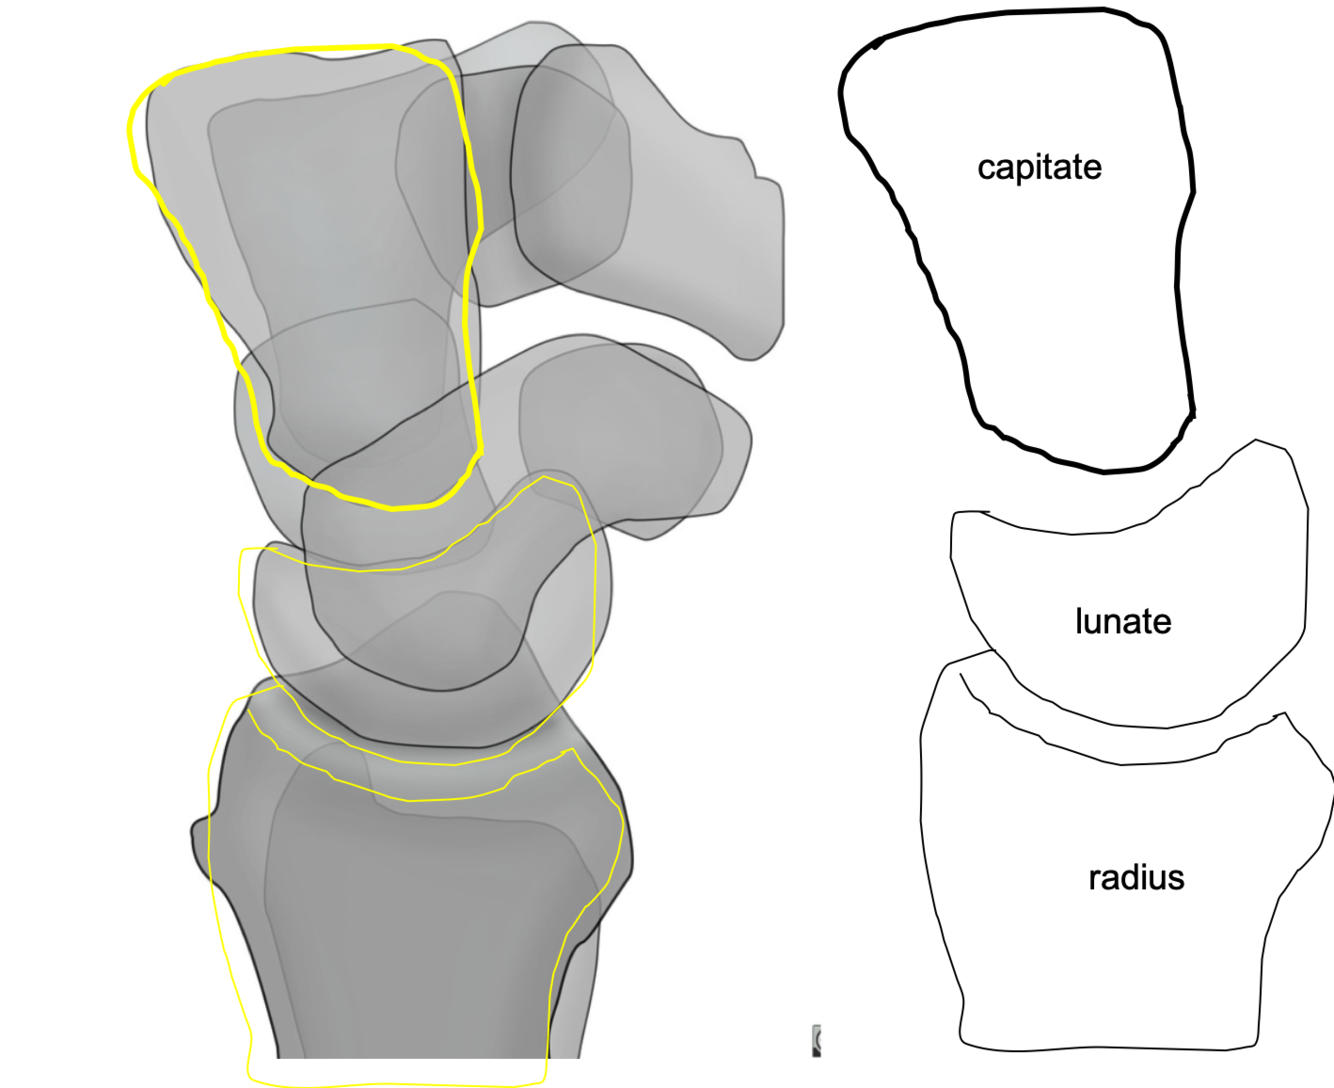

What is the difference between perilunate dislocation vs lunate dislocation?

Perilunate dislocation: lunate aligned with radius, but capitate is NOT aligned with the lunate

Lunate dislocation: lunate is dislocated volarly, but the capitate is still aligned with the radius.